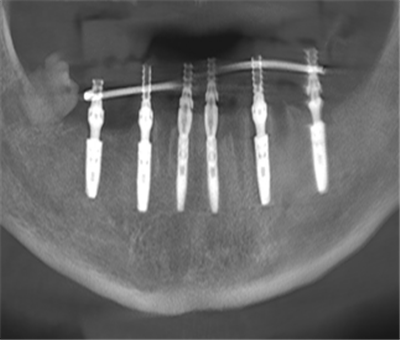

“创伤小、精度高,传统手术难度太大了!”毕主任和团队反复琢磨,先为赵先生制作了一副活动义齿调整,最后决定使用口腔种植机器人为赵先生进行半口种植牙手术。经过全面评估及沟通知情同意,毕主任团队为赵先生下颌区域“量身定制”了精准微创的种植方案,部分下颌牙拔除后在下颌区域即刻种植6枚种植体,且种植体准确植入到预计的三维位置,位置控制偏差不超过0.3mm。

手术完成,毕主任笑着告诉赵先生:“特别顺利!种植体的植入位置与术前规划完全一致。机器人按照事先设置的标准路径进行操作,避免了常规种植手术中出现的人为视觉偏差和手动误差。此次手术后进行的CBCT检查显示,误差仅为0.2mm,精度非常高”。